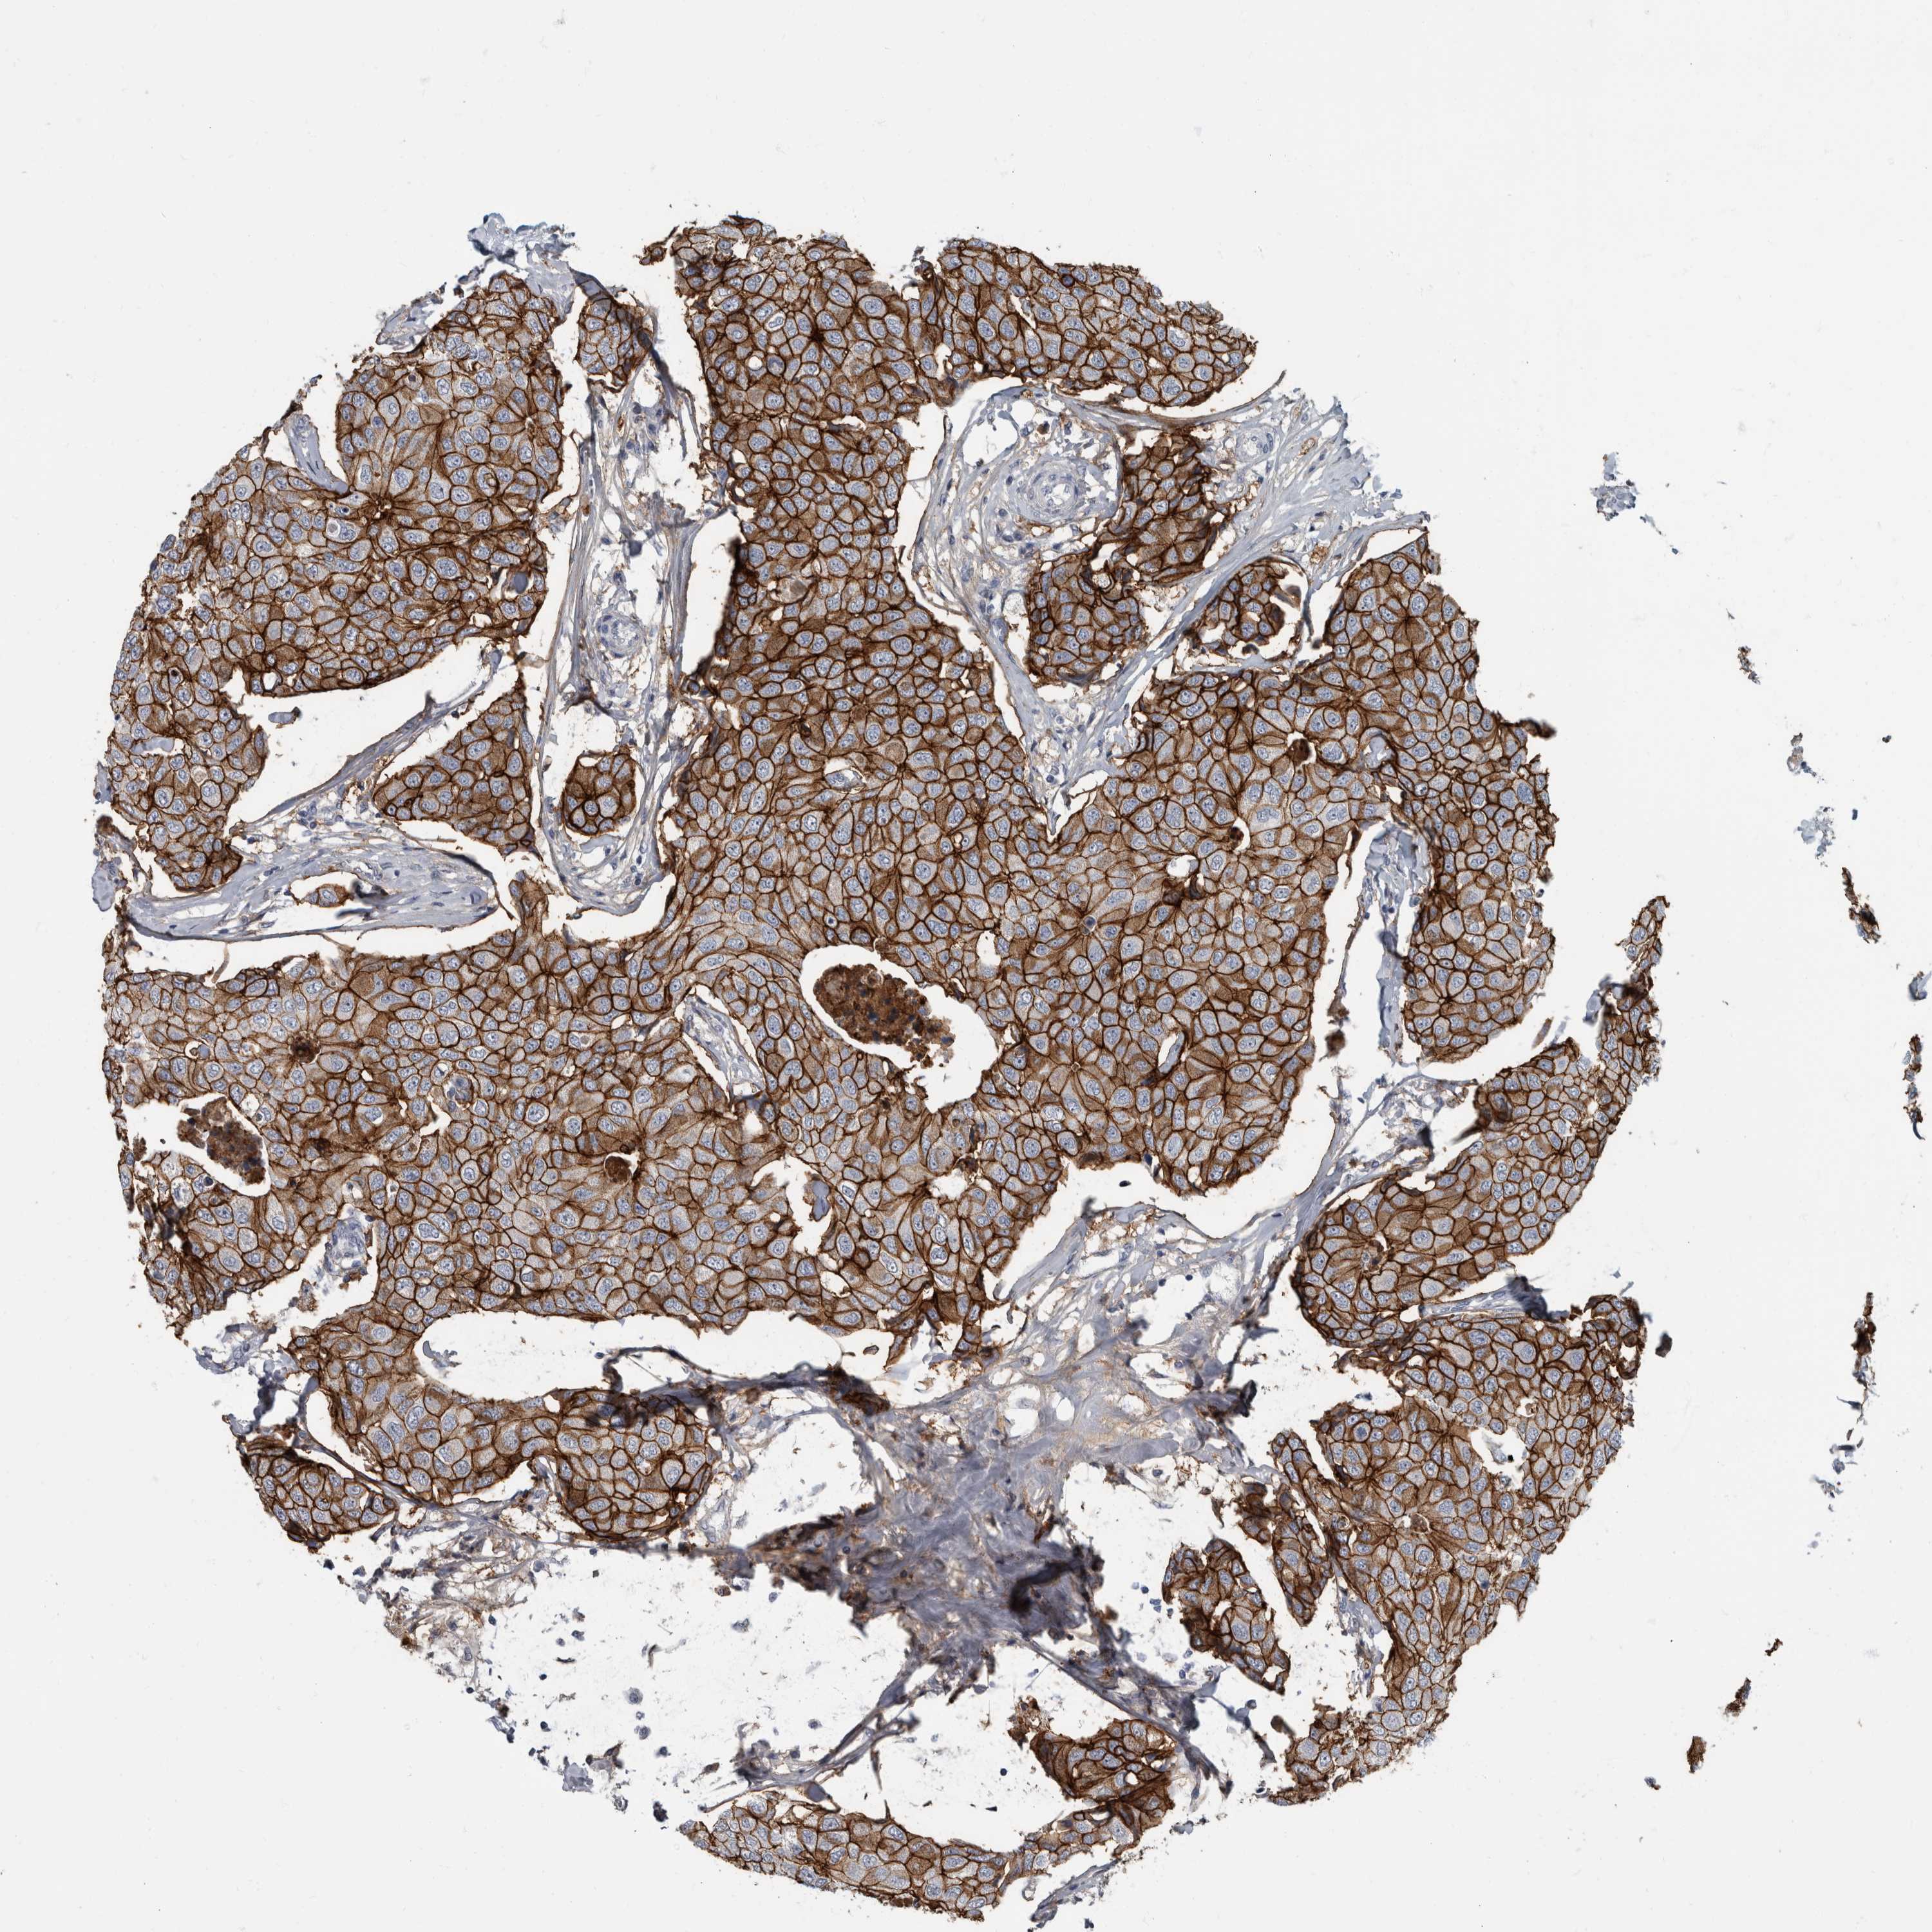

CANCER BREAST CANCER Show tissue menu

BRCA TCGA BRCA VALIDATION PROTEIN EXPRESSION